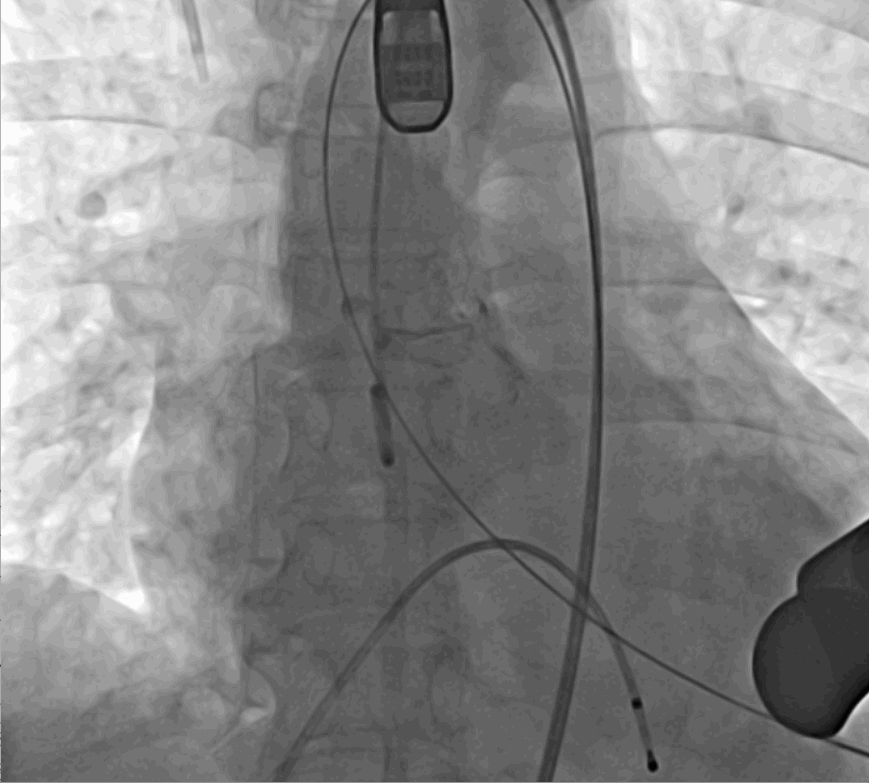

術中釋放定位鍵后DSA影像圖

術中瓣膜釋放過程